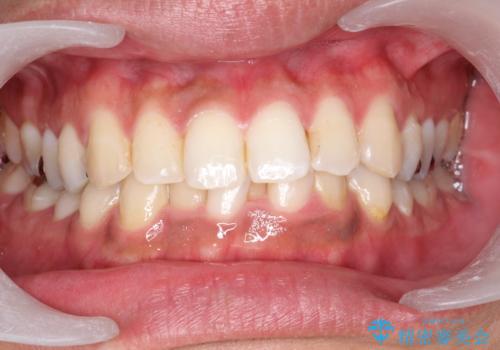

タバコによるヤニをPMTC(歯科医院での専門的クリーニング)で除去。